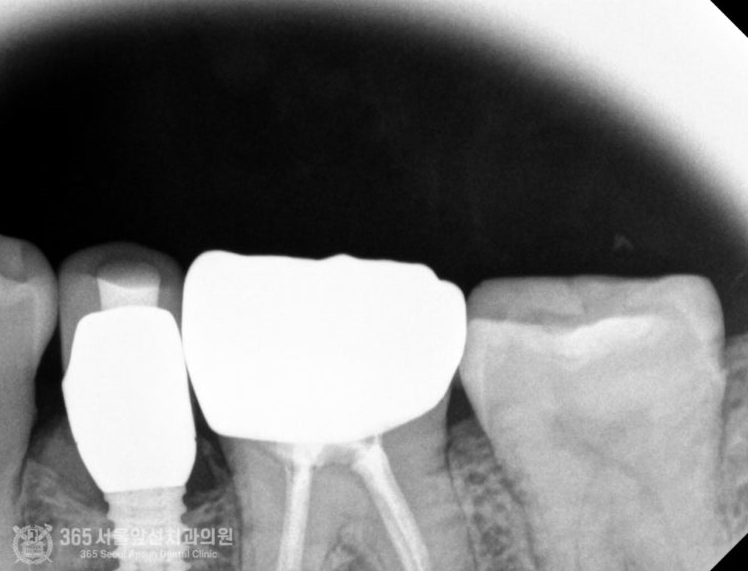

촬영일시 : 2024.07.12 신경치료가 마무리 된 후, 알맞게 크라운이 씌워진 모습의 엑스레이 사진입니다. 오늘은 치아우식증이 치아신경까지 진행되어 신경 치료 후 크라운으로 치료했던 환자분의 치료증례를 소개해드렸습니다. 앞으로도 좋은 치료로 지역 사회에 보답하는 미추홀구치과 365서울앞선치과가 되겠습니다 감사합니다 ㅎㅎ [치료기간: 2024년 6월1일 ~2024년 7월 12일] ※365서울앞선치과의원의 모든 포스팅은 각 진료과 의료진이 직접 작성합니다. 365서울앞선치과의원 블로그의 임상 케이스 게시물은 환자분께 의학적으로 정확하고 상세한 정보를 드리기 위해 각 진료과 의료진이 직접 작성하며, 모든 증례 사진은 본원 의료진이 직접 시술한 증례를 촬영한 것으로, 의료법 제23조, 제56조에 의거하며 환자분의 동의를 얻어 포스팅에 사용하였습니다. 또한 해당 케이스는 본 환자분의 치료 결과이며, 환자 상태에 따라 치료의 결과는 달라질 수 있습니다. |